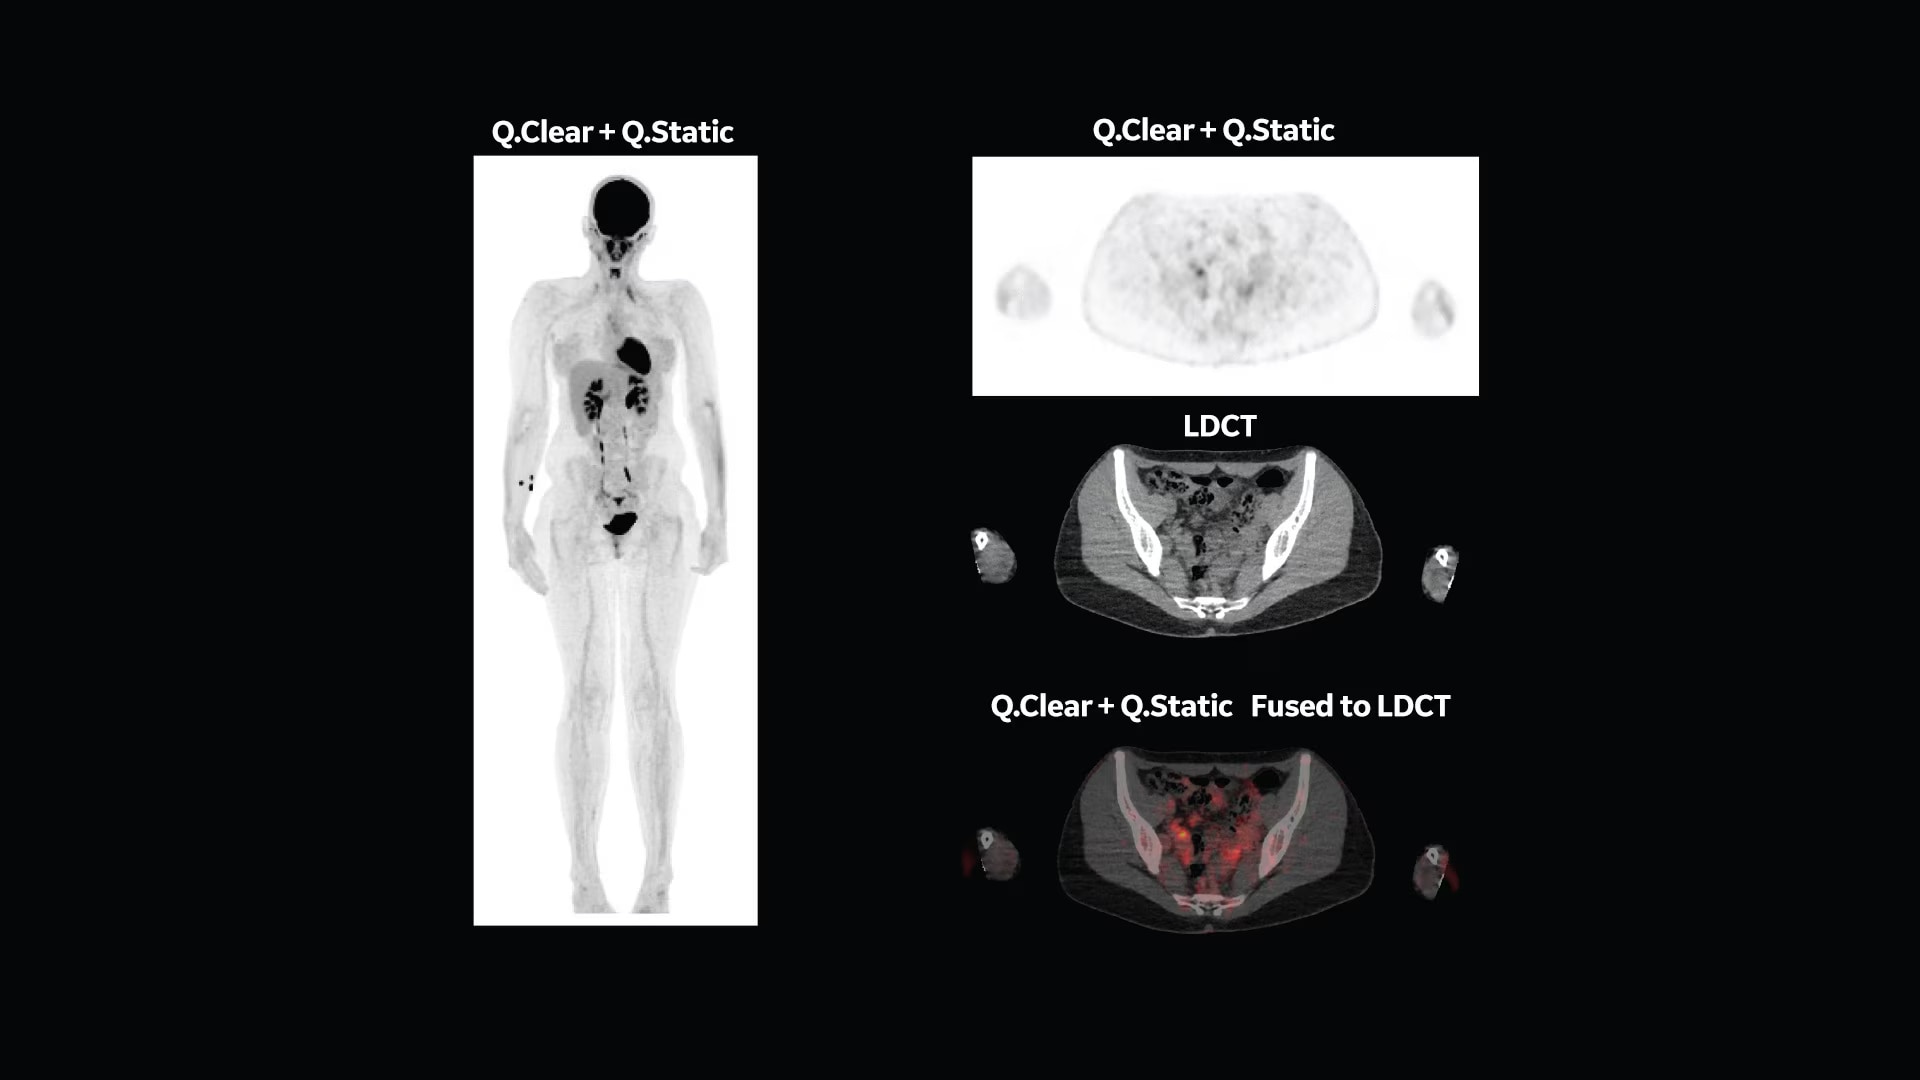

Q.Clear (BSREM): accurate data points to trusted treatment

Since its introduction, Q.Clear has delivered fast and efficient quantitation readings for confident diagnosis and precise treatment response assessment. Up to a 2x improvement in quantitative SUV (SUVmean). Up to a 2x improvement in image quality (SNR).